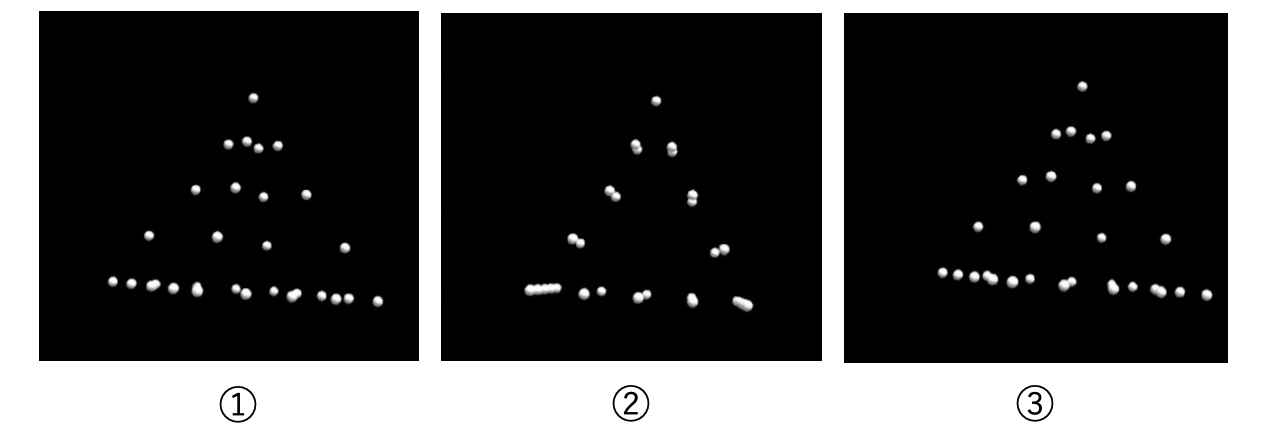

森本:突然ですが、上の3枚の画像をご覧ください。3枚ともただの点の塊ですが、左から順に見ていくと、ピラミッドのような物体が回転しているように見えませんか?

森本:たとえ2次元の画像であっても、動きによってそれを3次元に見せることができるのです。これは「structure from motion」と呼ばれる、動きによって立体感を感じる目の仕組みです。この時、背側視覚路の V5/MT 野から、腹側視覚路の下側頭葉の ITX 野への経路が刺激されていると言われています。次世代のSTS法では、視覚情報によってこの経路を強化することでより立体的に物体を捉えようとしています。